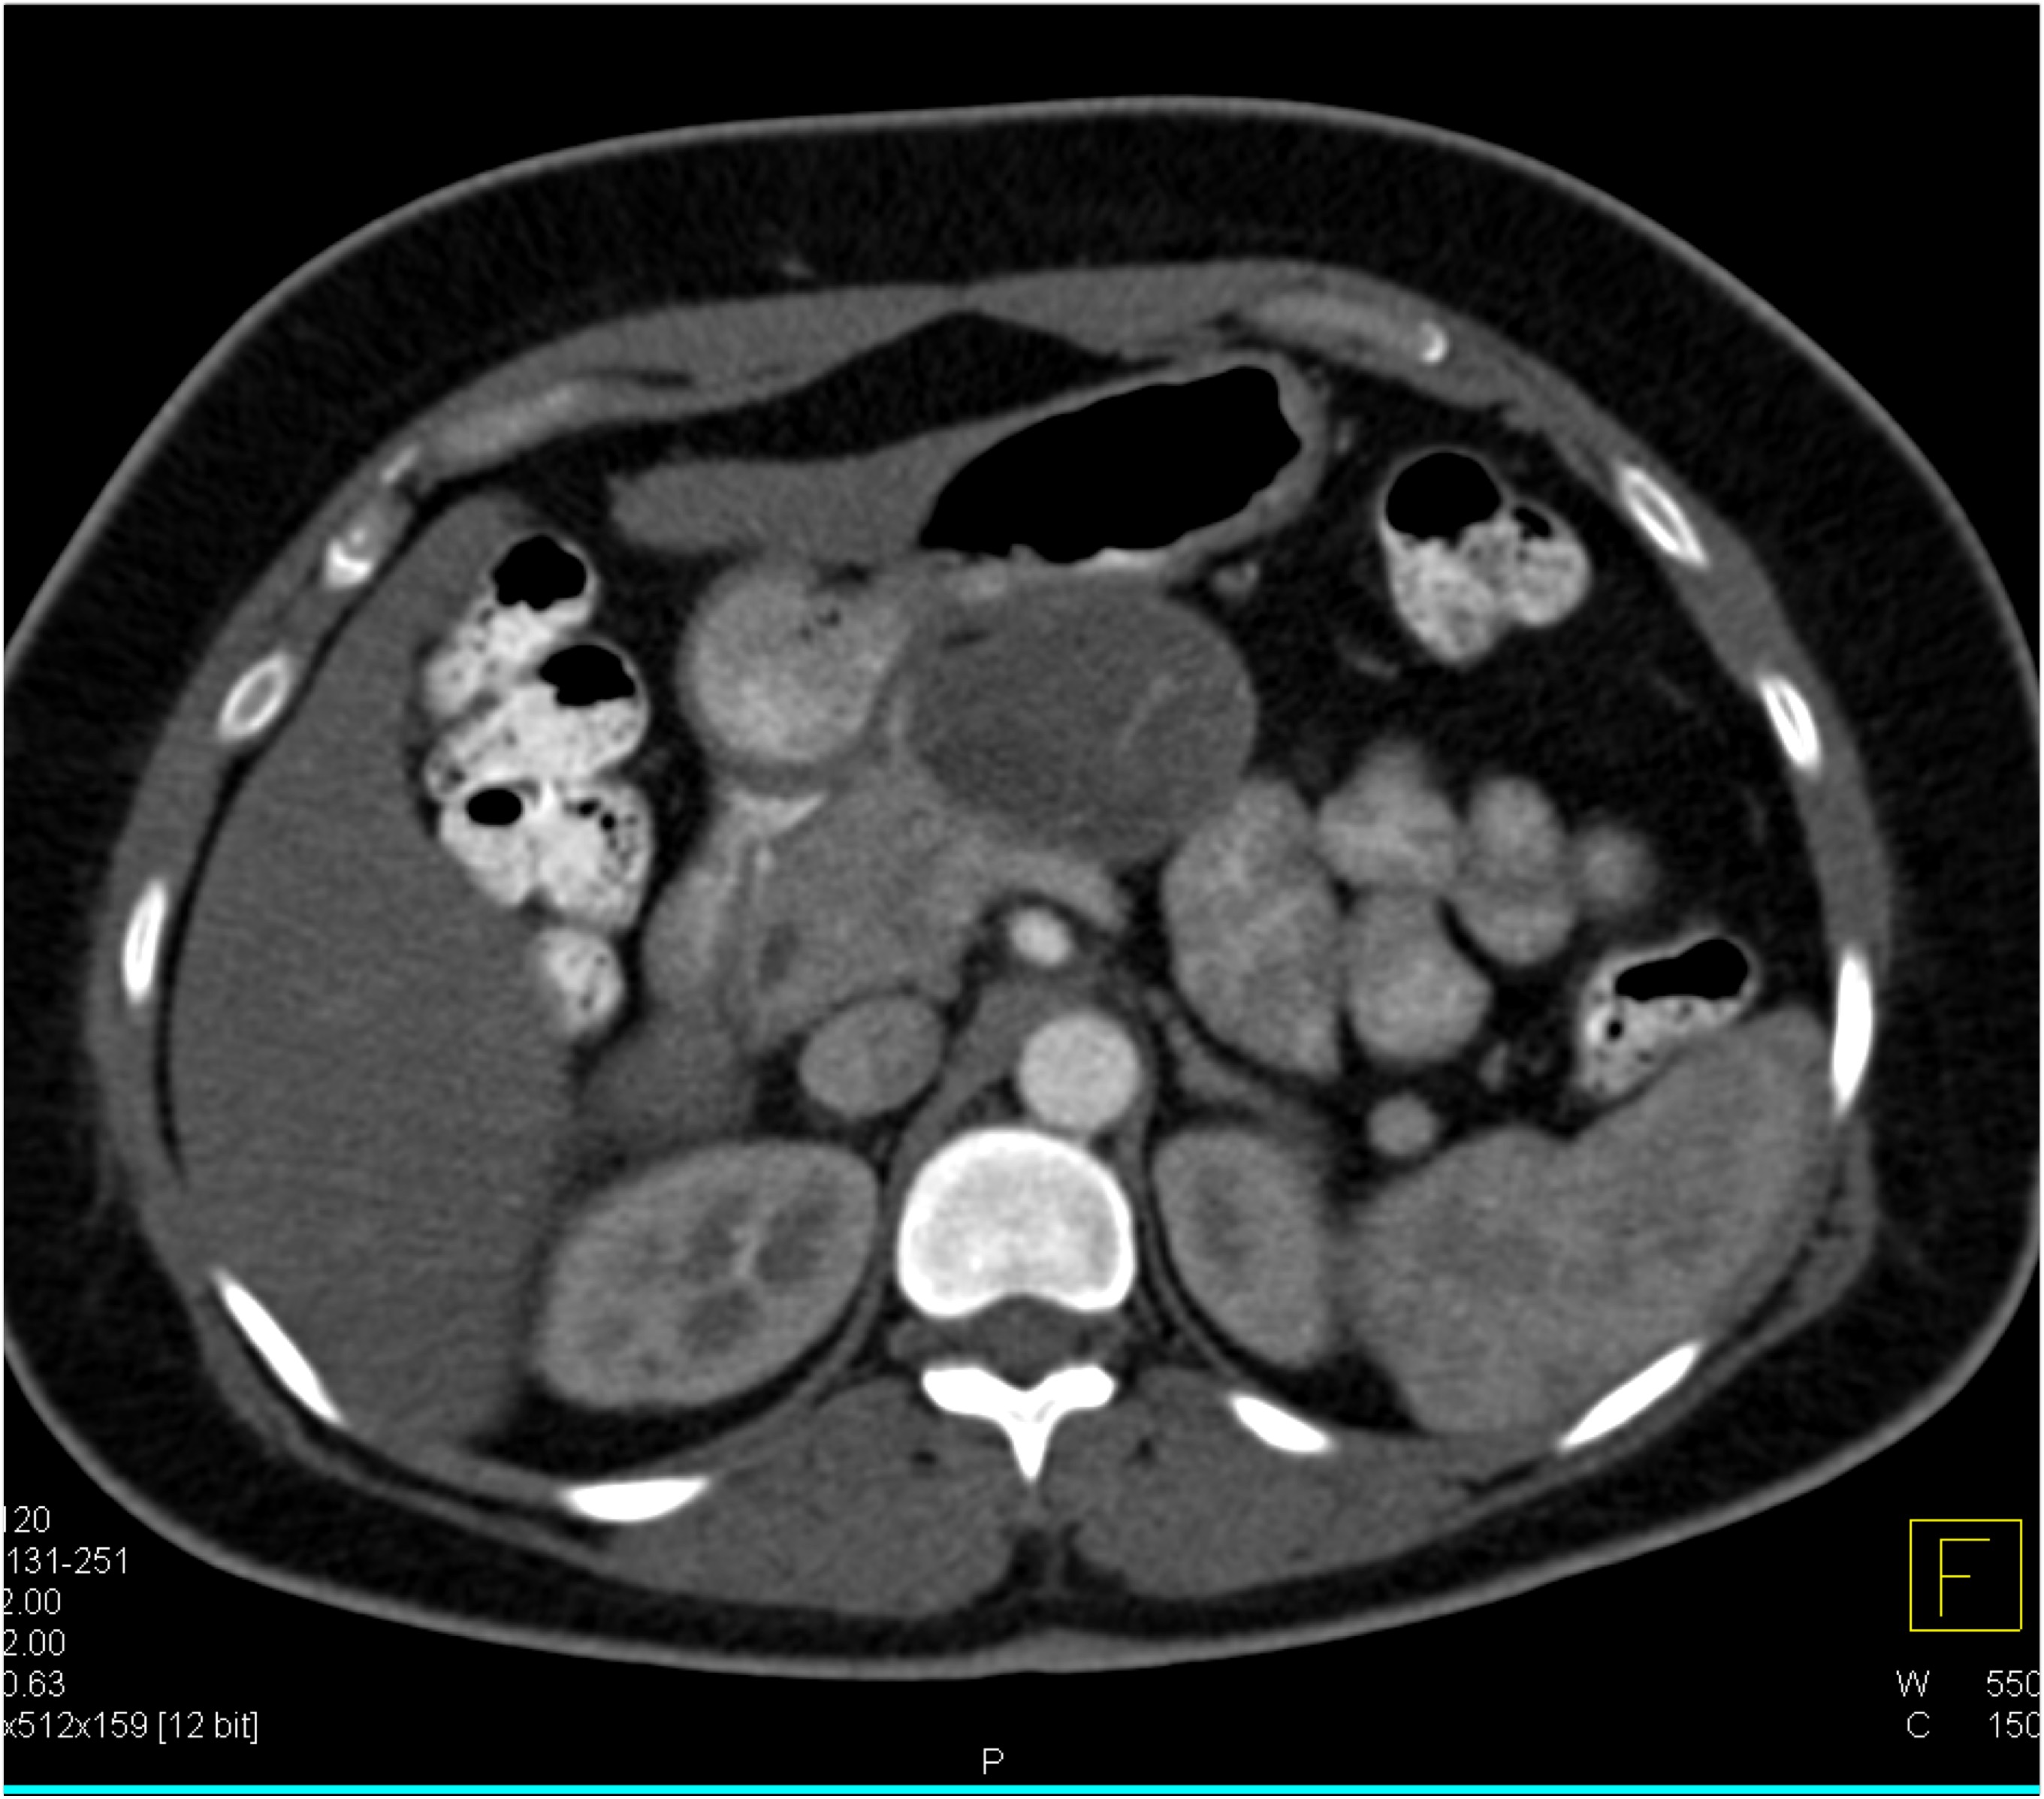

The most likely diagnosis in this 40ish year old female is

serous cystadenoma

mucinous cystic neoplasm (MCN)

IPMN

SPEN